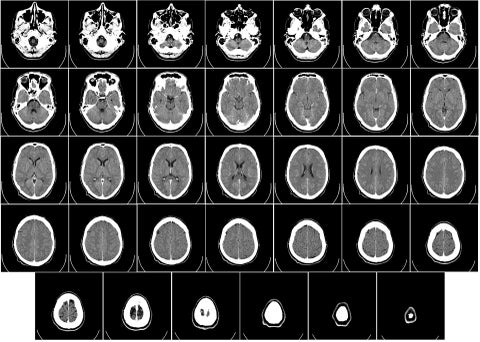

Conozca qué hábitos diarios están relacionados con la demencia. Crédito: Pixabay